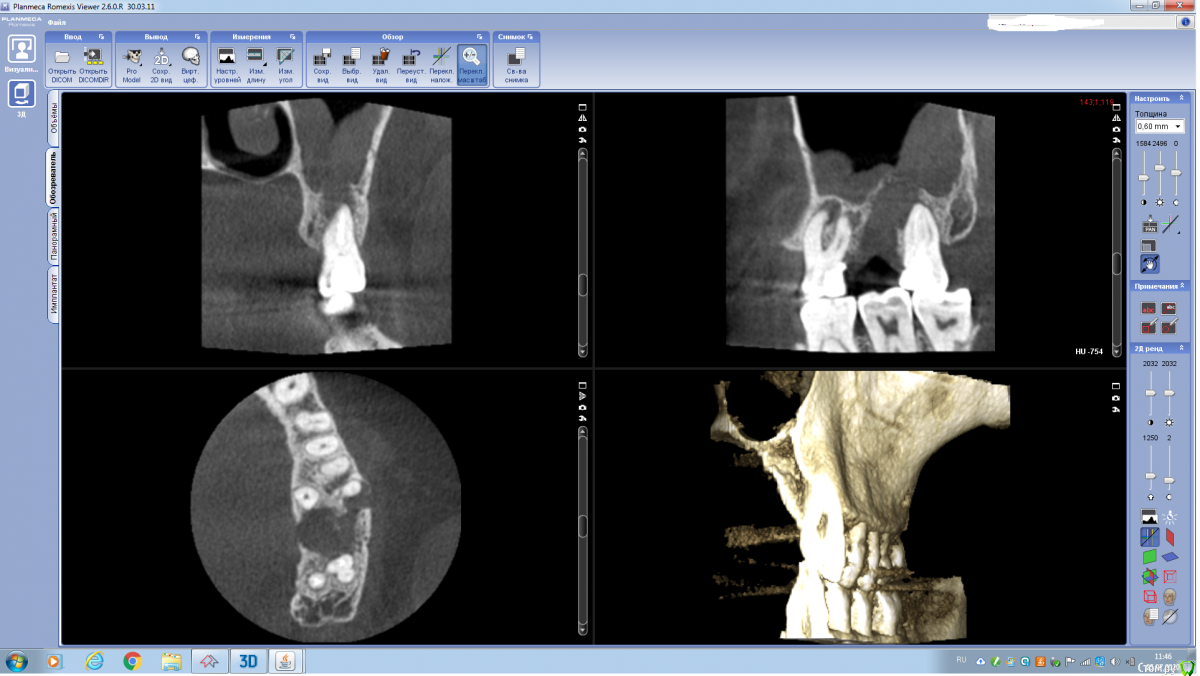

annda Опубликовано 25 июля, 2020 Поделиться Опубликовано 25 июля, 2020 (изменено) КТ до и после перелечивания.6 месяцев.Биокерамика с одиночным центральным гуттаперчевым штифтом. Изменено 25 июля, 2020 пользователем annda 2 1 Ссылка на комментарий

Redaksel Опубликовано 25 июля, 2020 Автор Поделиться Опубликовано 25 июля, 2020 КТ до и после перелечивания.6 месяцев.Биокерамика с одиночным центральным гуттаперчевым штифтом. Иванов до перелечивания.pngИванов 28.pngИванов 6 месяцев после лечения.png меня не смущает я за, начальство за такую цену нет)) Ссылка на комментарий